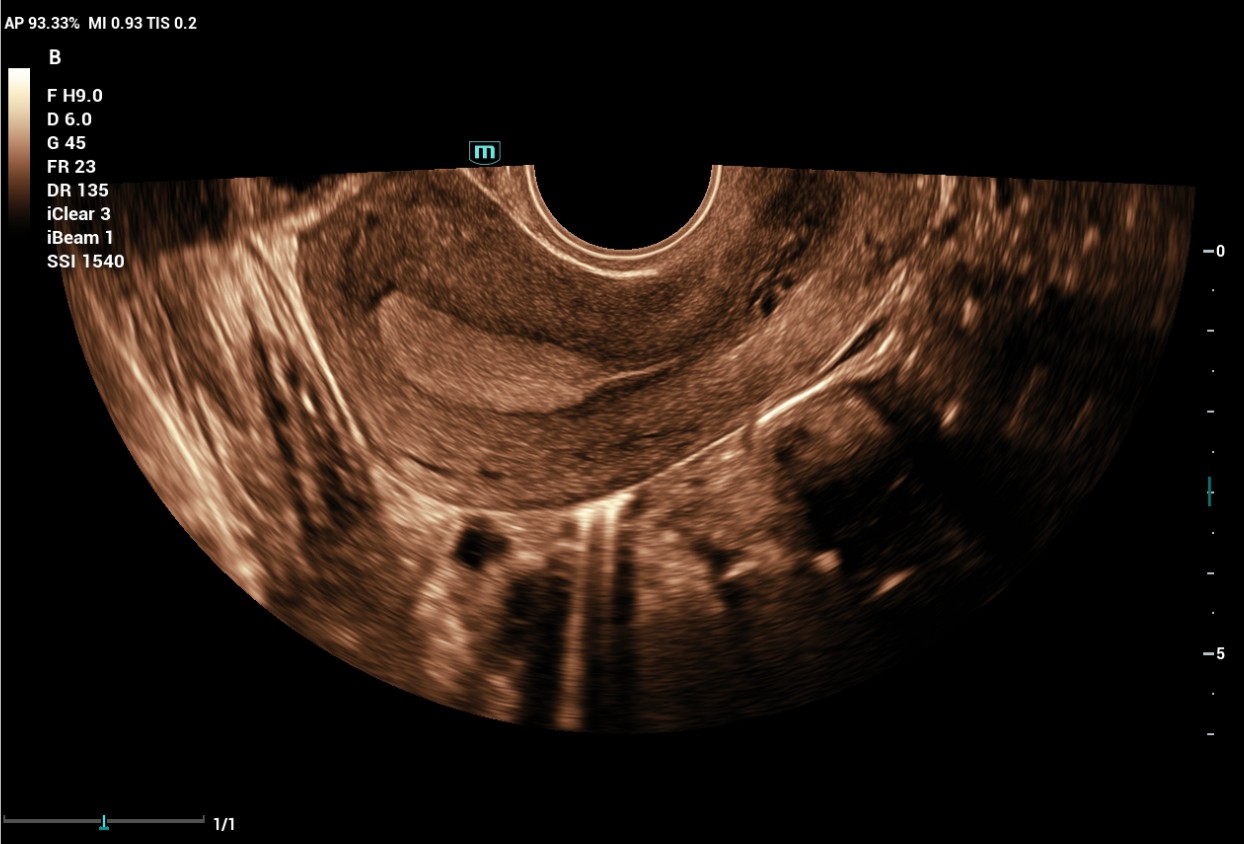

The Consona features new and concrete solutions, that efficiently help you to carry out smooth diagnoses for extensive type of patients. You will find highly powerful tools available on this series to keep you stay ahead in Obstetrics and Gynecology diagnosis.

Image Gallery